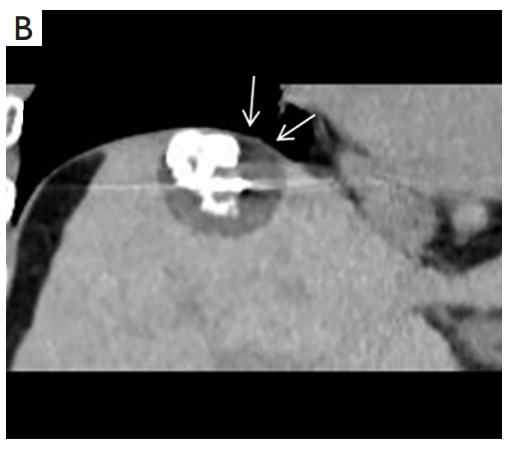

背景:肝癌是中国最常见的恶性肿瘤之一,发病率和死亡率都很高。虽然手术切除是最好的治疗方法,但大多数患者处于晚期或直到住院才有手术指征。对于单个肿瘤直径小于5厘米的患者,微创治疗与手术切除效果相当;多个病灶小于3个,单个病灶最大直径小于3cm;不侵犯血管、胆管、邻近器官和远处转移。虽然一些传统消融技术方式可以使部分患者受益,但不适用于特殊部位肝癌(定义为毗邻大血管、肝外脏器和重要结构的肿瘤)的治疗。冷冻消融作为一种相对较新的治疗方式,具有明显的冰球效果、疗效好、激活抗肿瘤免疫、并发症发生率低等优点,尤其适用于特殊部位肝癌患者的治疗。我们的研究目的是探讨CA治疗特殊部位肝癌的安全性、可行性和有效性。

① 在我们的研究中,技术成功率为100%。动态增强MR检查随访1个月,66例患者首次技术有效率为65例(98.5%),MR影像学未发现外周脏器损伤。中位随访时间14个月(范围2-28个月)。高危部位肝癌局部肿瘤进展率曲线:6、9、15和24个月的累积局部肿瘤进展率分别为10.2%、16.5%、20.9%和30.5%。